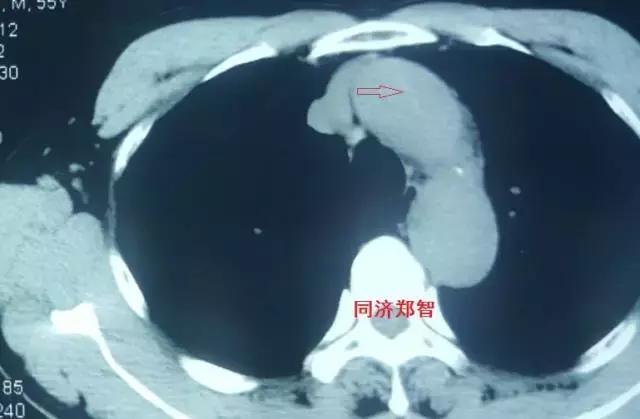

二

第二招 血管内膜征

正常情况下,主动脉的血管内膜在平扫CT中无法识别,但在某些特殊情况下,主动脉夹层及主动脉壁间血肿的平扫CT中也可以显示,从而帮助诊断。

病例六

平扫CT提示降主动脉内膜片影(白箭头所示),CTA显示为B型主动脉夹层。